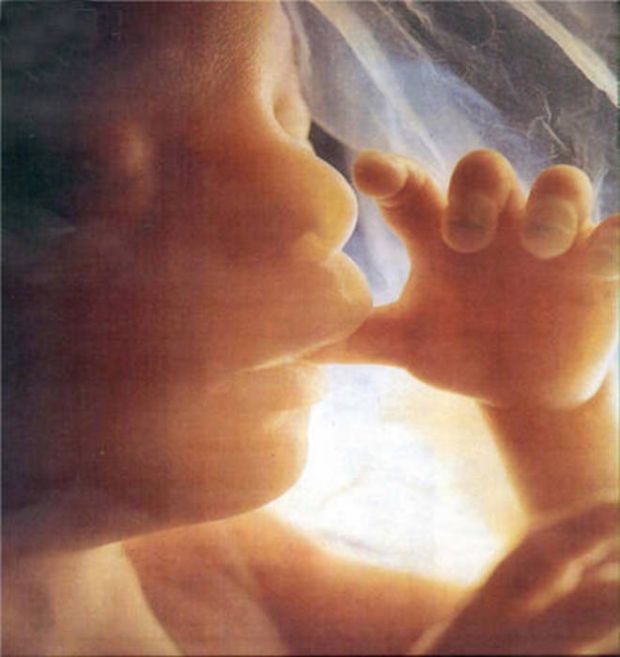

Per la prima volta è possibile vedere il feto in 3D, grazie a una tecnica basata sulla combinazione di immagini rilevate con la Risonanza magnetica e su tecnologie di realtà virtuale. Le immagini difficili da interpretare delle attuali ecografie potrebbero quindi in futuro lasciare spazio a quelle tridimensionali. Messa a punto e sperimentata nella Clinica di Diagnostica per Immagini di Rio de Janeiro, la nuova tecnologia è stata presentata al convegno della Società di Radiologia del Nord America. La tecnologia combina le immagini 3D, ottenute assemblando le immagini rilevate con la risonanza magnetica, e la realtà virtuale grazie al visore Oculus Rift. Le immagini 3D, infatti vengono viste attraverso il visore, che permette di vedere il feto 'da vicino': ''l'esperienza è meravigliosa – ha detto Werner – e le immagini sono più nitide e chiare rispetto a quelle dell'ecografia e della risonanza magnetica''.